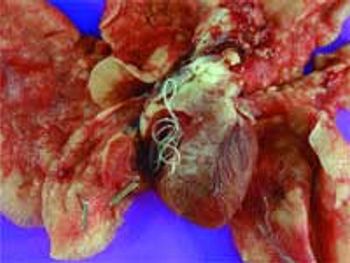

Cats are host to a variety of internal and external parasites. Despite the documented prevalence and zoonotic importance of these parasites, many pet owners and some veterinarians aren't convinced that comprehensive feline parasite control strategies are needed. This viewpoint may stem from the previous lack of safe, effective, and convenient broad-spectrum parasiticides and the difficulties in acquiring adequate fecal samples. Fortunately, newer broad-spectrum agents (Table 1), particularly those with label claims against heartworms and fleas, allow veterinarians to eliminate a higher percentage of feline parasites. Let's review some of the key feline parasites and discuss new strategies for controlling them.